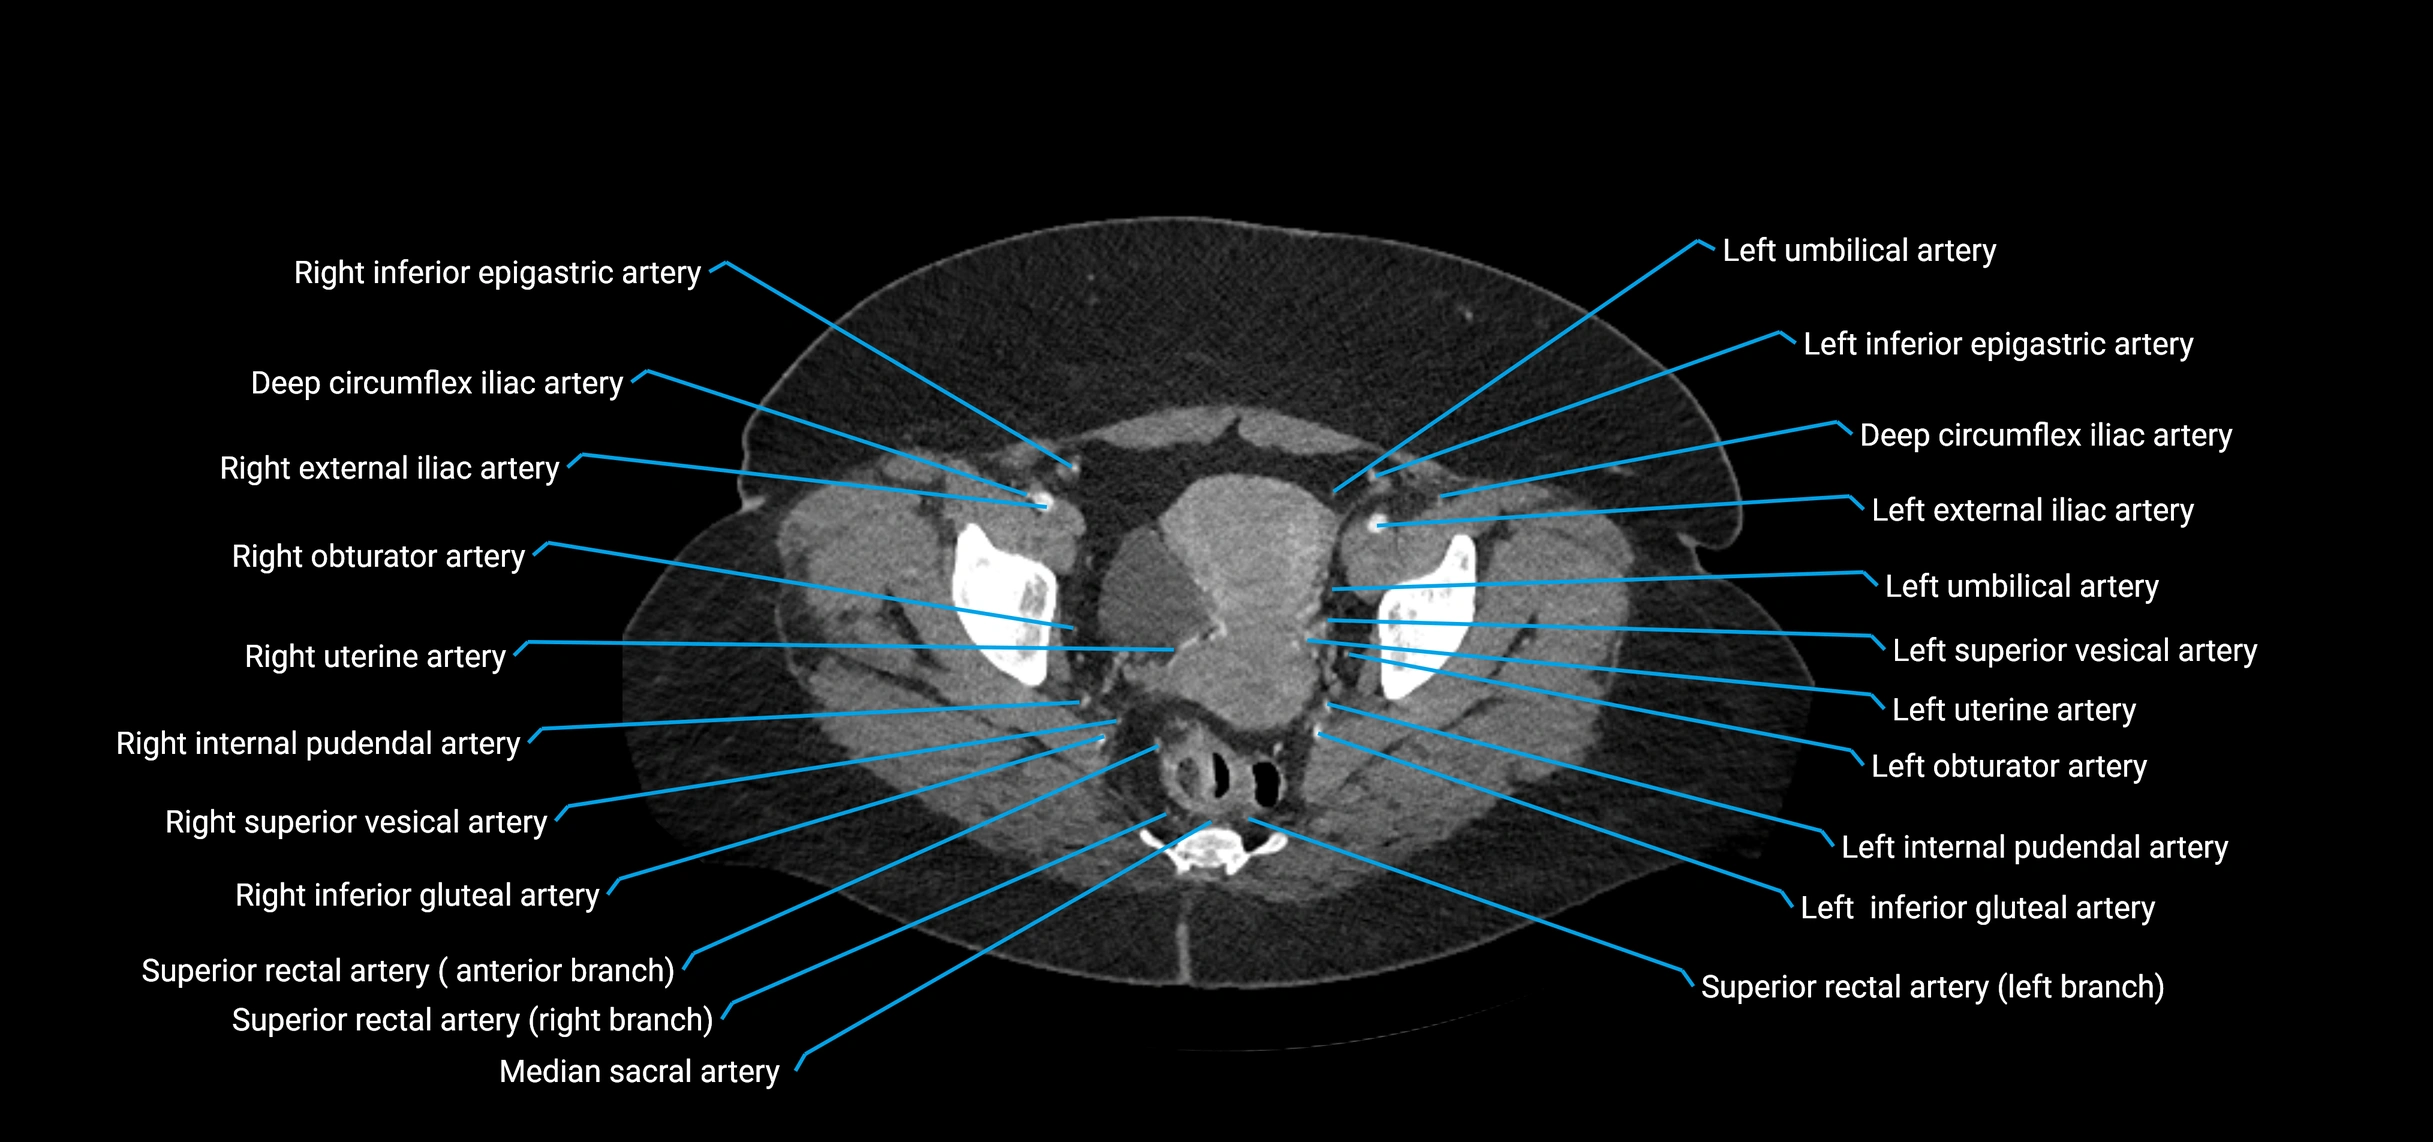

Contrast-enhanced CT (CTA):

• Gold standard for abdominal aortic imaging

• Provides excellent detail of lumen, wall, aneurysm, thrombus, and branch vessels

• Multiplanar and 3D reconstructions help in aneurysm measurement, stent graft planning, and dissection evaluation

• Detects acute rupture, traumatic injury, or occlusion with high sensitivity